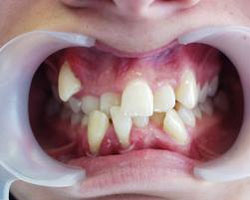

- *Răng mọc chen chúc:

- Răng mọc chen chúc là tình trạng các răng sắp xếp lộn xộn, không ngay ngắn trên cung hàm , răng mọc không đều, các răng khấp khểnh do thiếu chỗ (răng quá to hay xương hàm cung răng quá nhỏ không đủ chỗ để các răng sắp xếp).